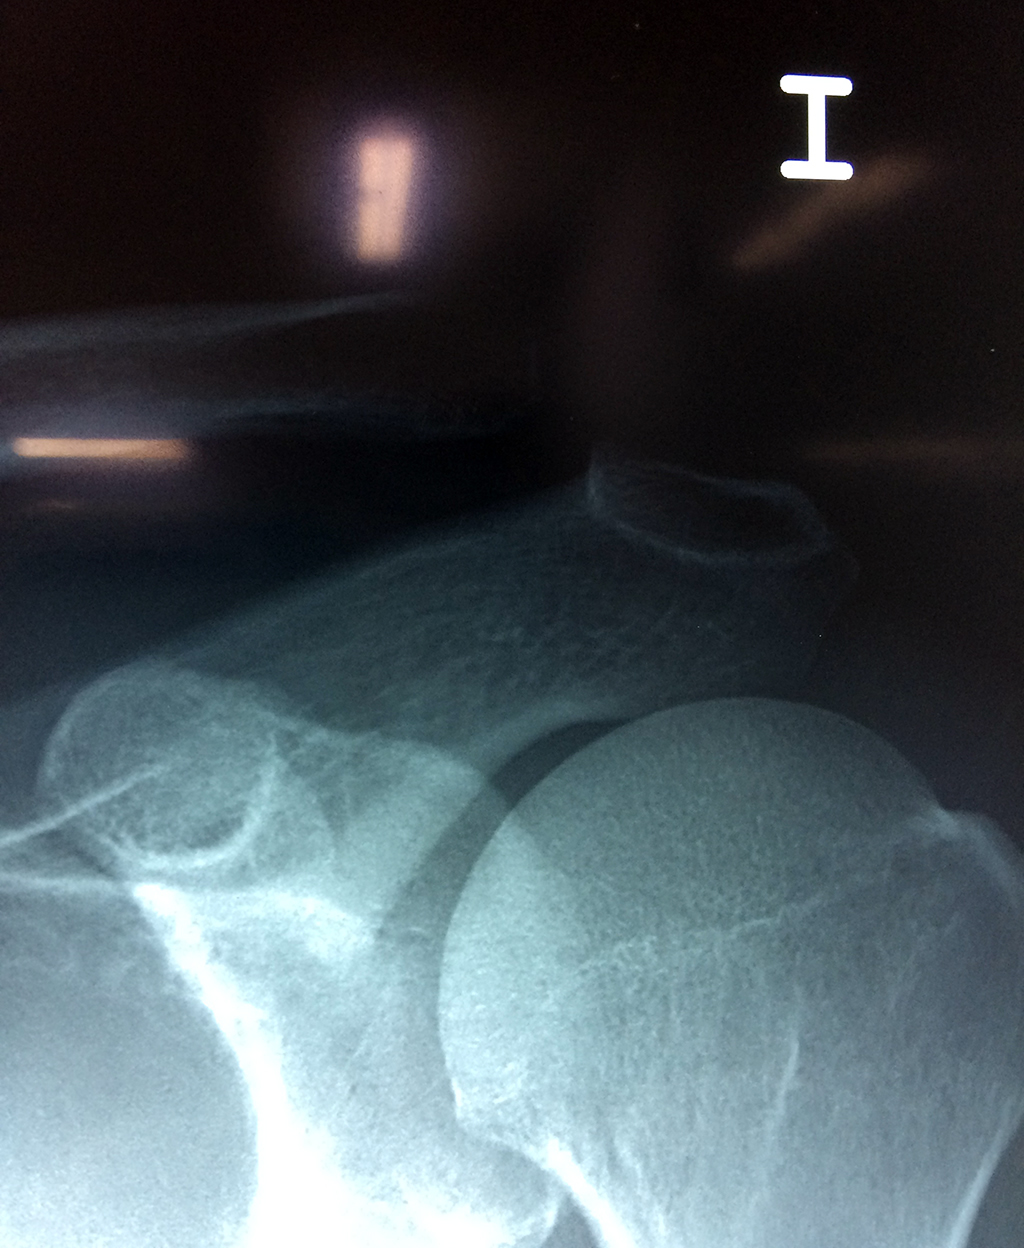

Cirugias en El Salvador - Clavícula

La clavícula es un hueso largo, con forma de "S" itálica, situado en la parte anterosuperior del tórax. Junto con la escápula forman la cintura escapular. Se puede palpar por toda su longitud y se extiende del esternón al acromion de la escápula, siguiendo una dirección oblicua lateral y posterior.

Se considera el único medio de unión entre el miembro superior y el tórax. A pesar de su aspecto, similar al de un hueso largo, posee una estructura semejante a la de un hueso plano, ya que carece de epífisis y de diáfisis, lo que la harían entrar dentro de la clasificación de hueso largo. Carece de un canal medular propiamente dicho.